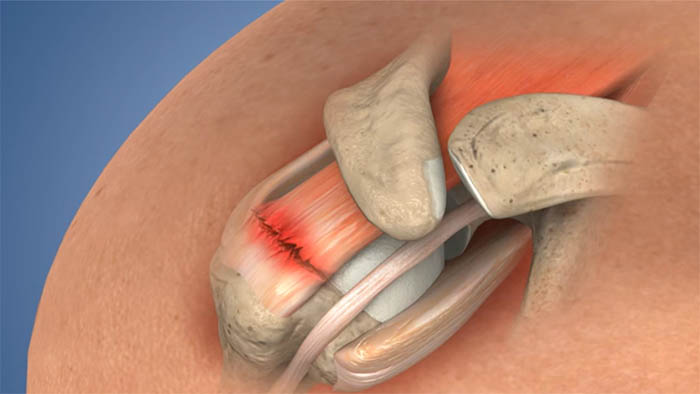

Swimmer’s shoulder, or impingement syndrome caused by repetitive shoulder movements, can lead to damage and tearing of the

Arthroscopic Labral Repair is a surgical procedure employed to address Labral tears that lead to shoulder instability. These